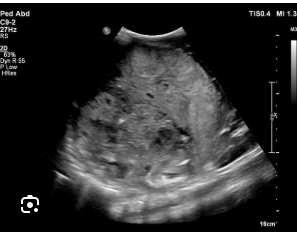

echinococcal cyst

echinococcal cyst (squiggle lines is the water lily sign)